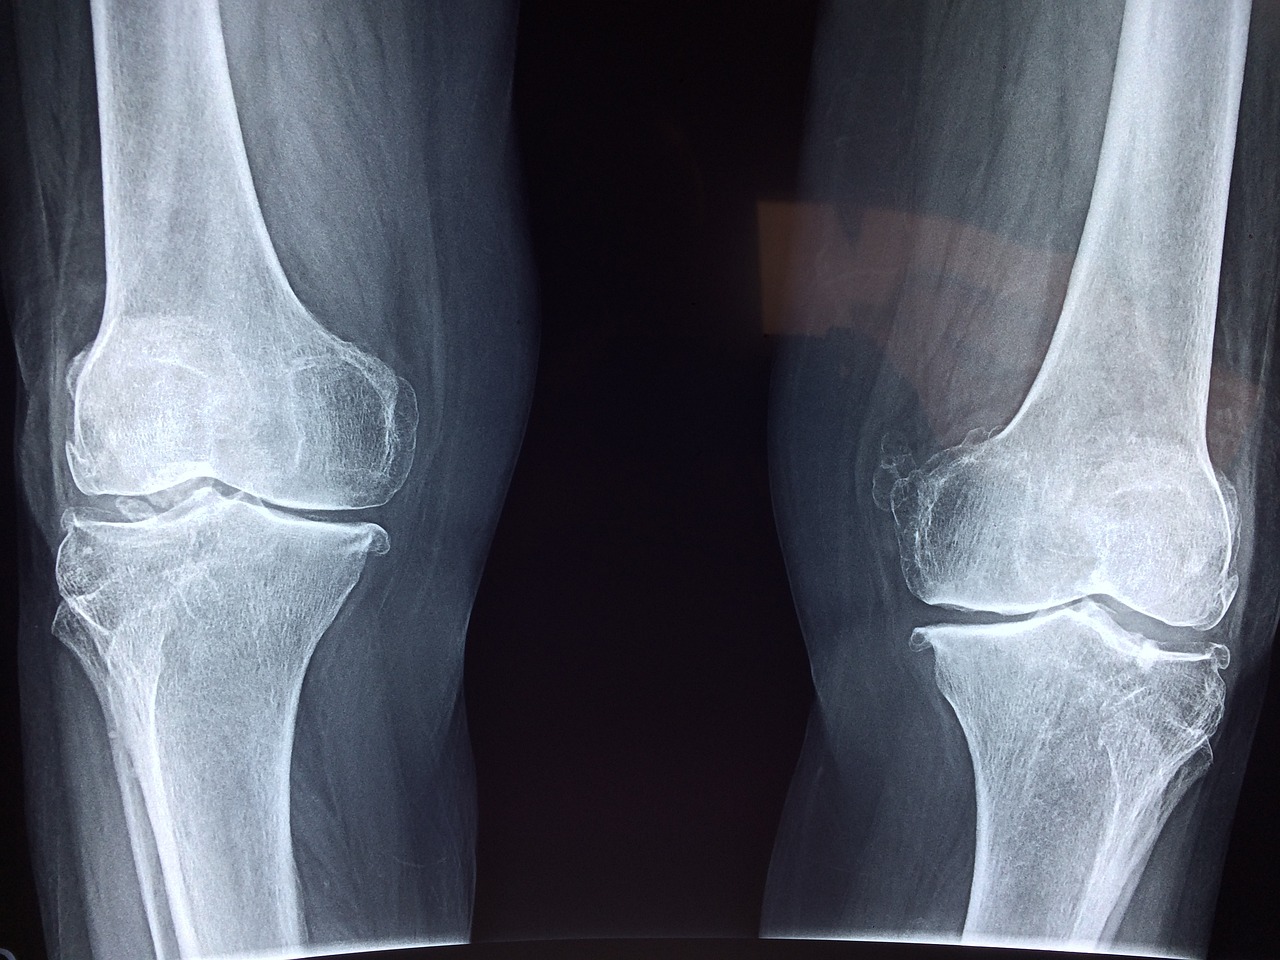

확실히 스테로이드를 고용량으로 장기적으로 쓰게 되면 골밀도에 영향을 줄 수 있습니다. 그에 관한 논문도 있습니다. 하지만 신경치료할 때 쓰는 약들은 고용량으로 쓰지 않기 때문에 골밀도에 거의 영향을 미치지 않습니다. 류마티스 관절염이나 여러 관절염, 근육통에 스테로이드를 쓰지만 골밀도에 영향을 줄 정도의 용량이 들어가지 않기 때문에 상관이 없습니다. 거기다 매일 맞는 것도 아니고 가끔 주사를 맞는 정도라면 뼈건강에 영향을 주지 않는다고 하네요~ 스테로이드를 과량으로 장기간 쓴다면 뼈에 영향을 줄 수 있지만 잘 조절해서 쓰면 오히려 만성 통증을 줄여주어 생활을 더 윤택하게 만들어 준다고 합니다. 이제 뼈가 녹을 걱정 없이 신경차단술을 받으시면 되겠습니다~